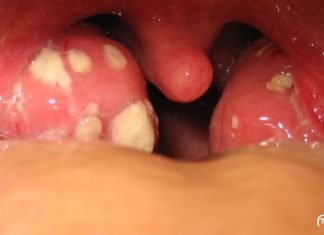

როგორ მოვიშოროთ ტონზილიტი და ტონზილიტი? მეთოდი რომელიც არ იცი და Შენ...

ტონზილიტი არის ინფექციური დაავადება, რომელიც აზიანებს ერთ ან მეტ ტონზილს,ჩვეულებრივ პალატინს, გამოწვეული ბაქტერიული ან ვირუსული ინფექციით.ტონზილიტის მთავარი სიმპტომია ყელის ტკივილი. ეს საშინელი დაავადებაა.

არსებობს მრავალი...